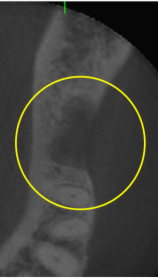

抜歯のう胞摘出

Perio Wave+Er:YAGレーザー+コールドレーザーで治療した箇所の経過です。

左から直後、1ヶ月経過時、2ヶ月経過時の画像です。

骨再生の確認をした際の動画です。

画像をクリックすると、youtubeにジャンプします。

骨再生

骨再生した箇所にインプラントを埋入します。

CTで治療計画を綿密に練ったうえで行いました。